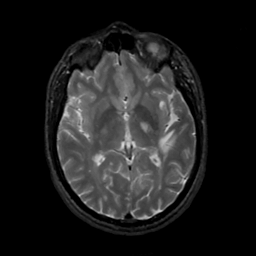

MR Study #3, February 24, 1991 -- Slice #25

[Home][Help][Clinical][Tour 1][Tour 2] Slice 25